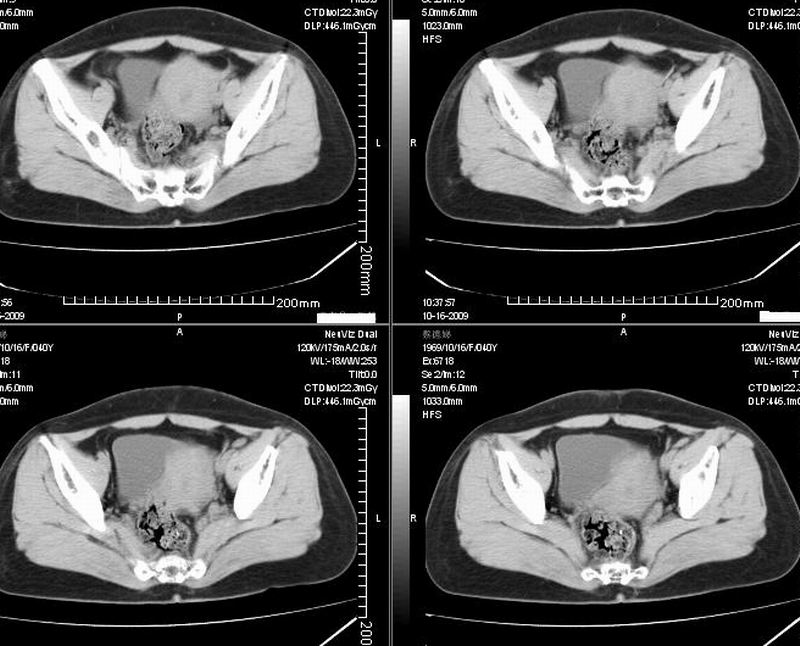

女:40y:下腹隐痛1周+,无其它不适,这个子宫会太一点吗?有临床意义吗?

宫腔内有积液,考虑炎症可能

形态不规则,不能除外肌瘤可能。

子宫偏左,略显增大,期内可见低密度改变,考虑宫腔积液可能。

子宫偏左,略显增大,期内可见低密度改变,考虑宫腔积液可能。 不能除外肌瘤可能。

子宫体积稍增大,其内见低密度影。考虑宫腔积液可能。

子宫不规则的增大 宫腔内积液 有多种考虑

1 子宫肌瘤

2 子宫腺肌症

3 子宫内膜炎

4 月经期 (宫腔内积血)